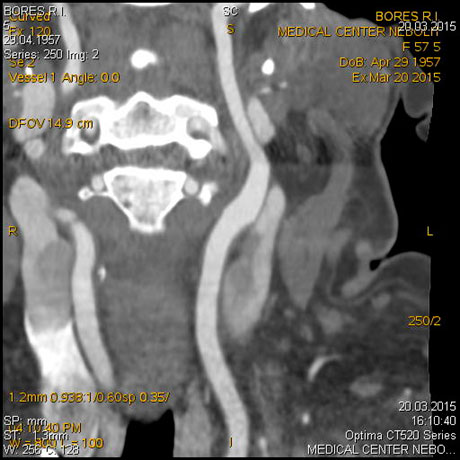

МСКТ-ангиография сосудов головного мозга

МСКТ высоко чувствительна в диагностике атеросклеротических кальцинированных, ,,мягких,, бляшек. В большинстве клиник метод МСКТ стал основным методом диагностики заболеваний сосудов сонных артерий, грудной, бюшной аорты, периферических пртерий.

Показания:

- диагностика сосудистых заболеваний (аневризмы, стенозы, мальформации, аномалии развития)

- Выявление венозного тромбоза

- Подозрение на острое кровотечение